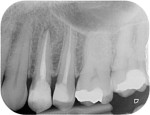

Post removal cases

Premolar retreatment